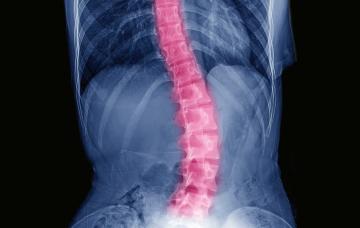

Escoliosis

La escoliosis es una desviación de la columna vertebral que origina una curva. La gravedad, el pronóstico y los síntomas dependerán de la magnitud de la curva, la edad de aparición, y la localización y características de la lesión.